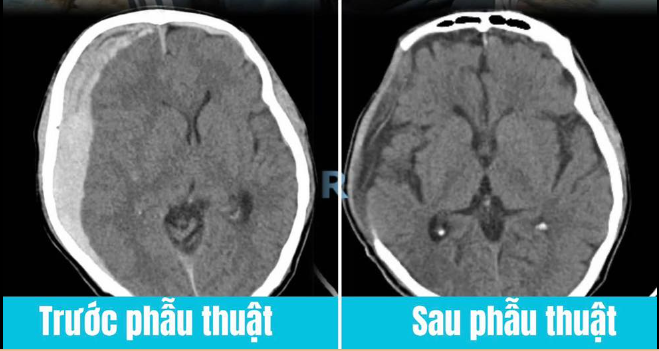

Ngay lập tức, các bác sĩ chỉ định chụp CT sọ não cho ông H. Kết quả cho thấy bệnh nhân bị tụ máu dưới màng cứng hai bán cầu giai đoạn cấp tính, kèm hình ảnh tụ máu dọc liềm đại não và lều tiểu não phải. Khối máu tụ gây chèn ép não thất bên phải, làm đường giữa não bị đẩy lệch sang trái 9mm (độ II), đe dọa trực tiếp đến tính mạng.

Trước tình trạng nguy kịch của người bệnh, ê-kíp Khoa Hồi sức Tích cực – Chống độc phối hợp với Khoa Ngoại Thần kinh đã hội chẩn khẩn cấp và thống nhất chỉ định phẫu thuật mở sọ giảm áp kết hợp lấy máu tụ cấp cứu. Ca phẫu thuật được tiến hành kịp thời, nhanh chóng, giúp giải phóng sự chèn ép não và giữ lại sự sống cho người bệnh.

Sau phẫu thuật, ông H. được chuyển về Khoa Hồi sức Tích cực – Chống độc để tiếp tục theo dõi và điều trị. Suốt một tháng qua, với sự phối hợp chặt chẽ của các bác sĩ nội khoa, hồi sức tích cực, ngoại thần kinh và phục hồi chức năng, bệnh nhân đã hồi phục gần như hoàn toàn.

Hiện tại, ông H. đã xuất viện trong tình trạng khỏe mạnh, có thể tự đi lại, sinh hoạt và ăn uống bình thường.